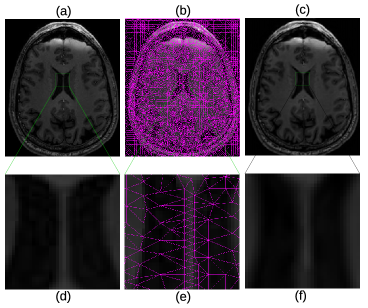

In Fig. 4, more details of the Lena experiment are shown. (a) is the original Lena image, the same as Fig. 3 (a). (b) is the mesh generated by the method outlined in section 2.1. (c) is the recovered image, which is the same as Fig. 3 (e). To visually see the generated mesh and compare the difference between the original and restored images, Fig. 4 (d)–(f) are the zoomed-in views of (a)–(c), respectively. As the results show, the mesh quality is high enough for subsequent numerical analysis and the the recovered image is very close to the original one. As a matter of fact, the restored image looks smoother due to the smooth radial basis functions used, and the sharp edge features are well preserved. Fig. 5 shows the original brain MRI, its generated mesh, and the result of ARBF interpolation using intensities on triangle centers with the MQ basis function. The zoomed-in views show the quality of mesh and restoration as well. Fig. 6 shows another MRI experiment of breast. Fig. 7 shows a CT-scanning experiment. From all these examples, one can see the effectiveness of the proposed approaches for image mesh generation and feature-preserving restoration.